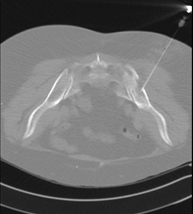

- TC Pelvis ósea Exploración radiológica que mediante un sistema de rayos X y detectores que giran alrededor del paciente, reconstruyendo las imágenes por ordenador (TC Multidetector), permite el estudio de huesos, músculos y articulaciones de la pelvis. Exploración radiológica que mediante un sistema de rayos X y detectores que giran alrededor del paciente, reconstruyendo las imágenes por ordenador (TC Multidetector), permite el estudio de huesos, músculos y articulaciones de la pelvis.

- TC Sacroilíacas Exploración radiológica que mediante un sistema de rayos X y detectores que giran alrededor del paciente, reconstruyendo las imágenes por ordenador (TC Multidetector), permite el estudio de las articulaciones sacroiliacas, y descartar enfermedades inflamatorias, traumáticas o degenerativas. Exploración radiológica que mediante un sistema de rayos X y detectores que giran alrededor del paciente, reconstruyendo las imágenes por ordenador (TC Multidetector), permite el estudio de las articulaciones sacroiliacas, y descartar enfermedades inflamatorias, traumáticas o degenerativas.